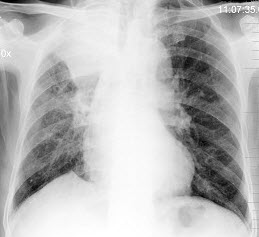

24、单项选择题

男,22岁,感胸痛且大汗淋漓就诊,X线检查如图,最可能的诊断是()

A.正常胸片

B.左肺肿瘤

C.左侧肺气肿

D.左侧气胸

E.支气管囊肿